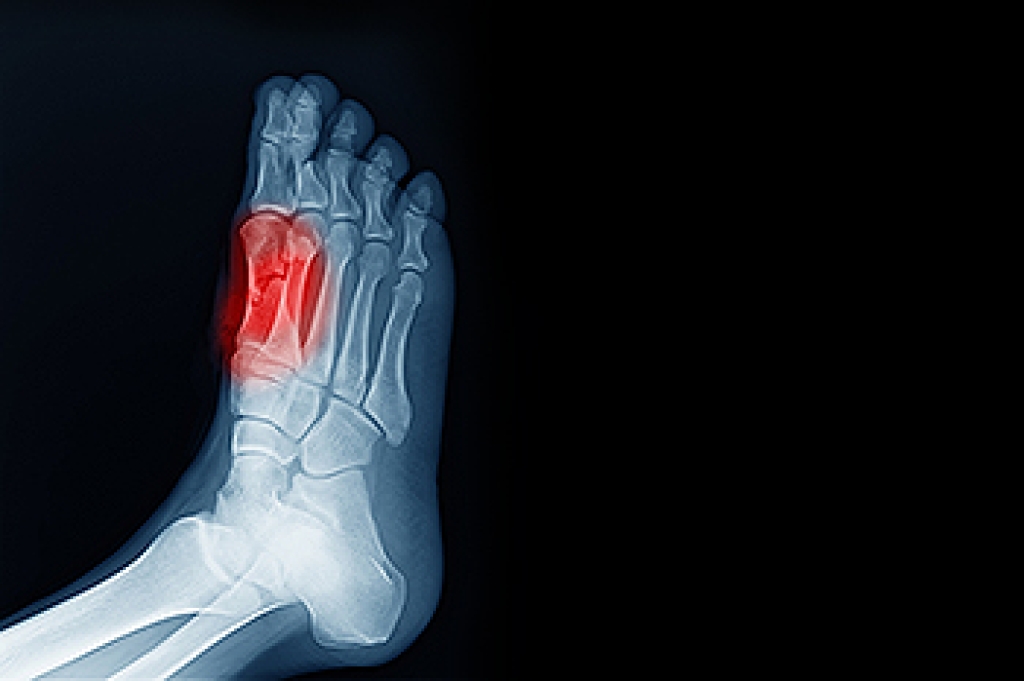

Sesamoiditis is a painful condition that affects the sesamoid bones, which are the small bones located beneath the big toe joint in the foot. These bones act as pulleys, aiding in movement and providing support for the tendons. Sesamoiditis occurs when these bones become inflamed or irritated, typically due to overuse or repetitive stress. Dancers, runners, and individuals who engage in activities that involve high impact on the feet are particularly susceptible to this condition. Common symptoms of sesamoiditis include pain and swelling surrounding the base of the big toe, which may worsen with activity and improve with rest. In some cases, there may be difficulty bending or straightening the big toe. If you have pain in this part of your foot, it is suggested that you visit a podiatrist who can accurately diagnose and treat sesamoiditis.

Sesamoiditis is a condition of the foot that affects the ball of the foot. It is more common in younger people than it is in older people. It can also occur with people who have begun a new exercise program, since their bodies are adjusting to the new physical regimen. Pain may also be caused by the inflammation of tendons surrounding the bones. It is important to seek treatment in its early stages because if you ignore the pain, this condition can lead to more serious problems such as severe irritation and bone fractures.

Treatment for sesamoiditis is non-invasive and simple. Doctors may recommend a strict rest period where the patient forgoes most physical activity. This will help give the patient time to heal their feet through limited activity. For serious cases, it is best to speak with your doctor to determine a treatment option that will help your specific needs.